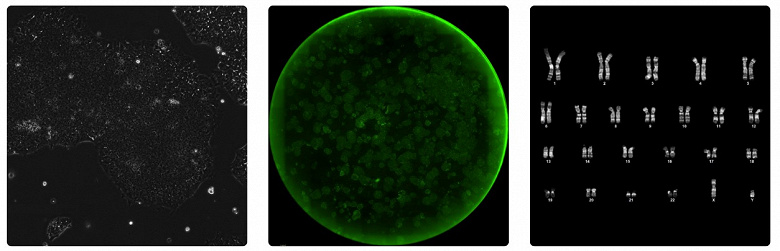

Используя GPT-4b micro, учёные спроектировали усовершенствованные варианты факторов Яманаки — белков, открытых нобелевским лауреатом Синья Яманака, способных превращать зрелые клетки в индуцированные плюрипотентные стволовые клетки. В лабораторных тестах новые белки обеспечили более чем 50-кратное усиление экспрессии маркеров перепрограммирования по сравнению с исходными факторами Яманаки. Эксперименты подтвердили лучшее восстановление повреждений ДНК и более высокий потенциал для клеточного омоложения. Такая активность моделировалась на клетках разных доноров и типов, причём созданные стволовые линии сохраняли плюрипотентность (свойство клетки, позволяющее ей развиваться во все типы клеток организма) и генетическую стабильность при многократном делении.

GPT-4b micro генерировала белковые последовательности, которые отличались от природных на сотни аминокислот, сохраняя и даже повышая эффективность перепрограммирования. Например, среди вариантов белка SOX2 более 30% новых конструкций превосходили природный аналог по ключевым биомаркерам, хотя в классических методах биоинженерии успешный результат получают менее чем в 10% случаев. Для другого белка, KLF4, показатель эффективности достигал почти 50%. Совмещение новых версий SOX2 и KLF4 давало ускоренный эффект — маркеры плюрипотентности появлялись в перепрограммированных клетках на несколько дней раньше, чем в контрольных экспериментах. Уже через 12 дней в культурах наблюдали массовое формирование колоний стволовых клеток; более 85% этих клеток запускали экспрессию ключевых генов, важных для стволовых линий.

Исследователи также отметили новые свойства белков: обработка клеток специальным коктейлем RetroSOX/KLF приводила к уменьшению повреждений ДНК, по данным маркера γ-H2AX, что важно для борьбы с признаками старения. Полученные стволовые клетки способны дифференцироваться во все три зародышевых слоя организма и сохраняли стабильность генома после многократного деления.